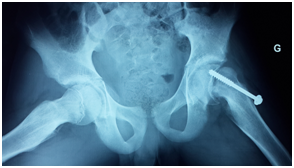

The admission examination finds a hemodynamically and respiratory-conscious conscious child, apyretic, weight at 40kg with extreme spasticity of the four limbs flexing. Both hips were adducted flexed at 80°C with pain in the mobilization of the left hip. The radiograph of the pelvis of the face showed a shift of the superior femoral epiphysis with respect to the metaphysis at the level of the left hip (Figure 1). The child was operated on day 2 of admission with a screw in situ (Figure 2). Operative follow-up was simple with radiological control, and the child was summoned for a month to check.

Figure 1 X-ray of the pelvis showing superior femoral epiphysiolysis on the left side (black arrow).